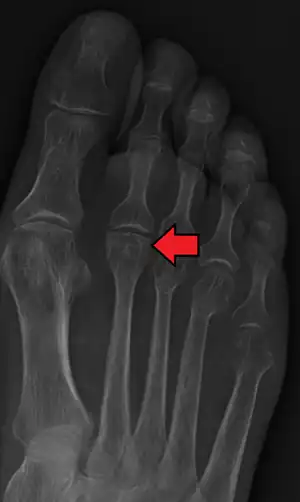

| Freiberg disease as seen on plain film | |

Freiberg disease, also known as a Freiberg infraction, is a form of avascular necrosis in the metatarsal bone of the foot. It generally develops in the second metatarsal, but can occur in any metatarsal. Physical stress causes multiple tiny fractures where the middle of the metatarsal meets the growth plate. These fractures impair blood flow to the end of the metatarsal resulting in the death of bone cells (osteonecrosis). It is an uncommon condition, occurring most often in young women, athletes, and those with abnormally long metatarsals. Approximately 80% of those diagnosed are women. [1]